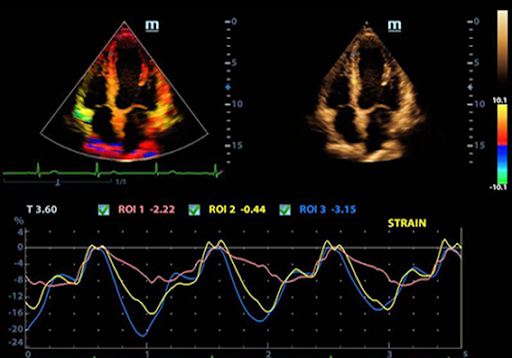

Режим деформации / скорости деформации

Позволяет получить полную оценку ишемической болезни сердца посредством визуализации показателей деформации / скорости деформации, обеспечивая детальное сопоставление различных участков миокарда.

Free Xros CM

Позволяет получить полную информацию о движении сердечной мышцы в различных фазах сокращения и одновременно определять степень синхронизации миокарда. Точность результатов обеспечивается высокой частотой кадров.